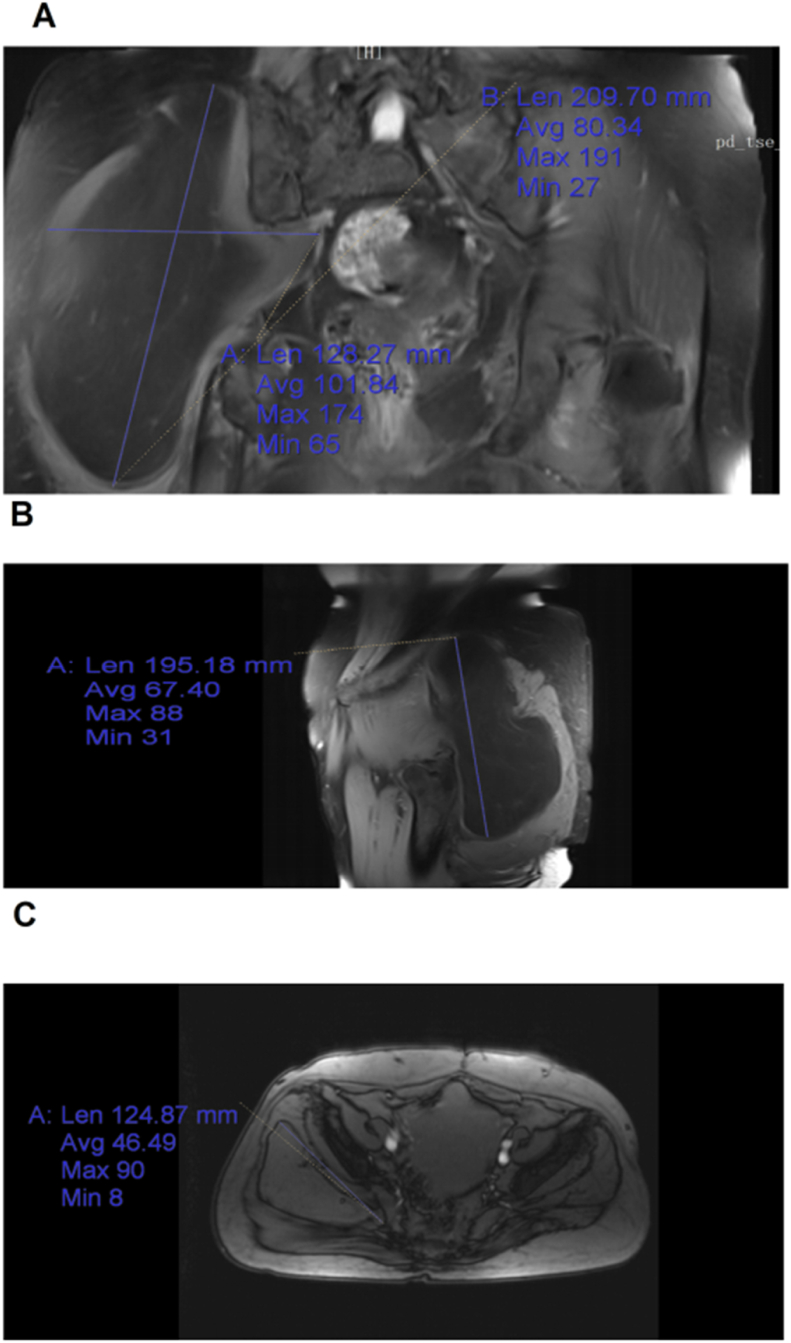

A 59-year-old Chinese woman, who was previously healthy, was admitted to the Department of Orthopaedics, Affiliated Hospital of Changchun University of Traditional Chinese Medicine, because of “right hip mass and right lower limb tingling for 6 months” and no obvious family or social history. Physical examination showed that the right buttock was swollen, the palpable size was 20 ∗ 13 cm, and the skin color and skin temperature were normal. The boundary is clear, there was no tenderness. The right lower limb of Lasegue sign is positive, the right lower limb was slightly numb and the blood supply was good. Auxiliary examination: MRI examination of sacrococcygeal bone revealed that a slightly shorter T2 signal of quasi-circular isometric T1 could be seen in the right gluteal muscle, and the boundary was clear, with the range of about 10.9 cm ∗ 9.6 cm ∗ 19 cm as shown in Fig. 1. Ultrasound of the right hip joint showed that the muscle layer of the right hip joint had a heterogeneous echoes of about 15.3 cm ∗ 5.8 cm ∗ 20 cm. CDFI showed that there was no obvious blood flow signal except lipoma. Preoperative examination ruled out the contraindications, and the operation time was determined according to preoperative discussion, ultrasound and MRI results.

Fig. 1.

A: Morphology of coronary mass on MRI; B: morphology of sagittal mass on MRI; C: morphology of transverse position mass on MRI.